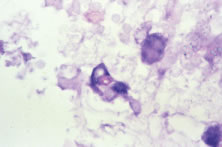

Both herpes simplex virus type 1 and herpes simplex virus type 2 (HSV-1, HSV-2) may cause ARN.20–22 In a single report, CMV particles were identified in and cultured from the retina of an enucleated eye of a nonimmunosuppressed patient suffering from bilateral ARN.23 VZV has been reported most frequently as the viral etiologic agent of ARN.2,3,24–27 We have demonstrated herpesvirus family viral particles in endoretinal biopsy specimens taken from patients in the active stage of the disease who showed an enormous viral load (Fig. 4). These studies, combined with the failure of many enucleated eyes with ARN to demonstrate evidence of viral particles, indicate that the virus is present only in the active stages of the disease and that a gliotic retina will not demonstrate the etiologic agent.28

Light microscopic examination of these retinas reveals full-thickness necrosis and loss of the retinal architecture.25,30,35 Within the necrotic retina, macrophages, plasma cells, and other inflammatory cells are found in addition to cells containing eosinophilic inclusions. There is a sharp demarcation between affected and nonaffected retina, suggesting cell-to-cell transmission of the virus. Arteritis manifests as endothelial cell swelling with occlusion of the vessel lumen, infiltration of the subendothelium with plasma cells, and inflammatory cell thrombi. When healing occurs, a thin glial scar replaces the necrotic neural elements. Herpesvirus capsids may be observed in electron microscopic specimens of actively infected retinal tissue but are not seen once healing has occurred and glial scar tissue replaces the necrotic retina.28,30